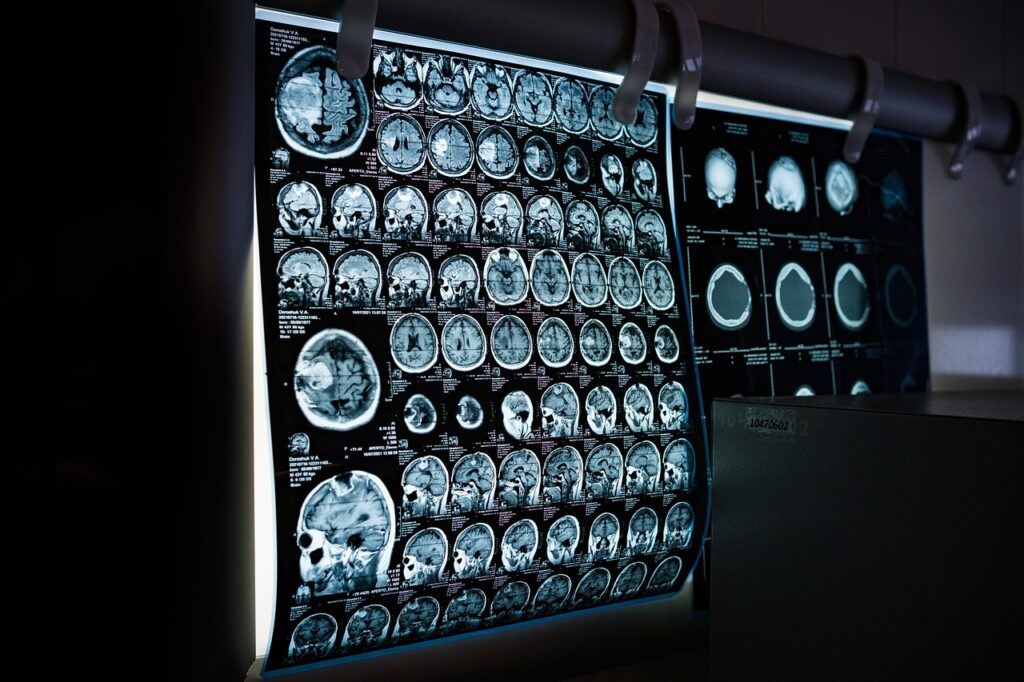

Harvardo ir Masačūsetso General Hospital tyrimas „Eight Weeks to a Better Brain“ atskleidė, kad vos per 8 savaites mindfulness meditacijos hipokampo srityje padidėjo pilkosios medžiagos tankis – srityje, atsakingoje už atmintį, mokymąsi, emocijų reguliaciją (Harvard Medical School). Kiti tyrimai rodo pokyčius ir prefrontalinėje žievėje bei insuloje – regionuose, kurie padeda išlaikyti dėmesį ir reguliuoti emocijas.

Naujausi tyrimai rodo, kad meditacija pagerina komunikaciją tarp smegenų sričių, atsakingų už emocijų apdorojimą, empatiją ir savistabą (PMC). EEG ir MEG tyrimai netgi rodo specifinius smegenų bangų pokyčius (theta, alpha), siejamus su ramybės ir dėmesio būsena.